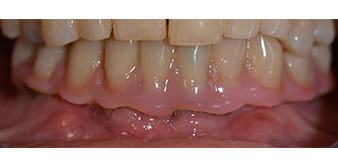

Following the time required for the osseointegration, the final impression of the implants could be performed and the final denture produced accordingly (Fig. 19 and 20). At this point, the dentist and patient were able to decide together whether to use a ceramic or acrylic veneer and a zirconium or metal framework. In this case, Dr. Pascu’s team decided on an acrylic veneer based on the unclear prognosis for the maxillary dentition and the fact that tooth 24 is elongated. This type of veneer is generally considerably easier to adapt and can thus be subsequently altered to reflect the new situation in the maxilla.